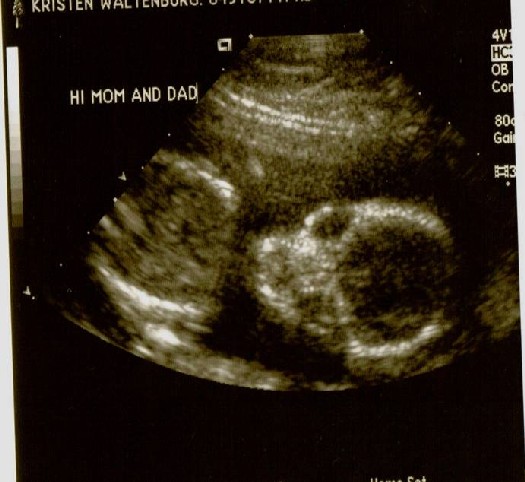

After following a strict schedule of how much water to drink, when to drink it, when to pee and when not to pee, Colby and I arrived at Kaiser for our big ultrasound appointment! The BIG day, when we would find out if we have a pink or blue bun in the oven!! While pacing up and down the aisle in a desperate attempt to stay in control of my bladder, my mom, Colby’s mom and his sisters join us for the long awaited peek. Finally! My name is called and I’m provided some relief as I lie down on the chair in the dark room. The nurse squirts some gel on my belly, which I was grateful to realize they warm it on this floor! She proceeds with the ultrasound, taking pictures for the doctor for about 20 minutes. I didn’t get a peek until the others were invited in. We saw distinct hands and feet, a big alien head, even an ear… but what we really wanted to see was obstructed by two little legs, crossed at the ankles. No angle could seem to enlighten us!! So, the nurse admitted that when she was taking pictures on her own, she got a possible view of what she thinks are boy parts, but since she couldn’t get back under there to verify it, she said she would print that picture and leave it to our interpretation. That’s where you come in. Please take a look at the pictures below. The one labeled “Gender” is the deciding factor. Once you’ve gotten a good look, please use the “post your comment” link at the bottom of this blog, and let us know if you believe it to be a boy or girl. Profile:

Alien Face: